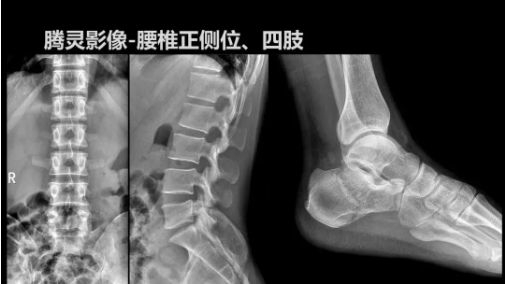

“騰靈”是安健科技的第四代動(dòng)態(tài)DR產(chǎn)品,可實(shí)現(xiàn)全科室應(yīng)用。如各類(lèi)常規(guī)的X線(xiàn)檢查、消化道檢查、骨科檢查、婦科、兒科檢查等。此外,安健科技為“騰靈”在真正意義上實(shí)現(xiàn)多科室、多功能診斷進(jìn)行了多項(xiàng)針對(duì)性設(shè)計(jì)。

其中包括SID范圍可調(diào)節(jié)能夠滿(mǎn)足多種類(lèi)攝影要求、球管角度可調(diào)節(jié)能夠滿(mǎn)足不同投照部位的需求、超低床體設(shè)計(jì)方便患者上、下床、360°可旋轉(zhuǎn)腳踏板降低擺位難度、可移除式濾線(xiàn)柵能夠滿(mǎn)足兒科等特定場(chǎng)景的計(jì)量要求、可升降操控臺(tái)方便醫(yī)生床旁操作等,并配置了全身拼接功能,最大程度上適配動(dòng)態(tài)DR產(chǎn)品的特點(diǎn)。

此外,“騰靈”為了能夠幫助醫(yī)生更快速、有效的定位病灶,還增加了多項(xiàng)精準(zhǔn)診斷保障功能,如支持動(dòng)態(tài)觀察診斷,實(shí)時(shí)高清點(diǎn)片等?!膀v靈”透視切換高清點(diǎn)片曝光,捕捉關(guān)鍵病灶診斷僅需0.8s,同時(shí)還支持圖像局部放大,醫(yī)生可自由切換15’12’和9’三種放大模式,另外,“騰靈”還支持視頻保存、回放功能,幫助醫(yī)生在檢查結(jié)束后通過(guò)回放查看細(xì)節(jié),為醫(yī)生的診斷增加信心。